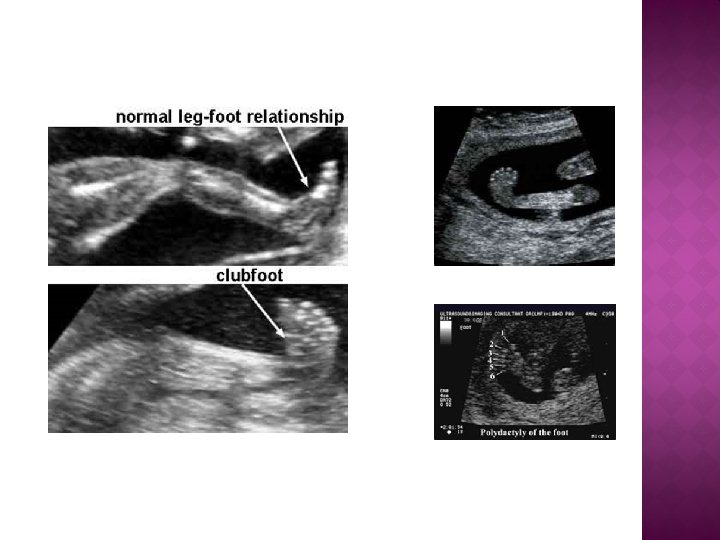

� EL VE AYAKLAR Preaxial /postaxial polidaktili Sindaktili Klinodaktili Hipoplazi /aplaziler Postural deformiteler: hitchhiker’s thumb, rocker -bottom feet, clubbed feet, hand, clenched hand